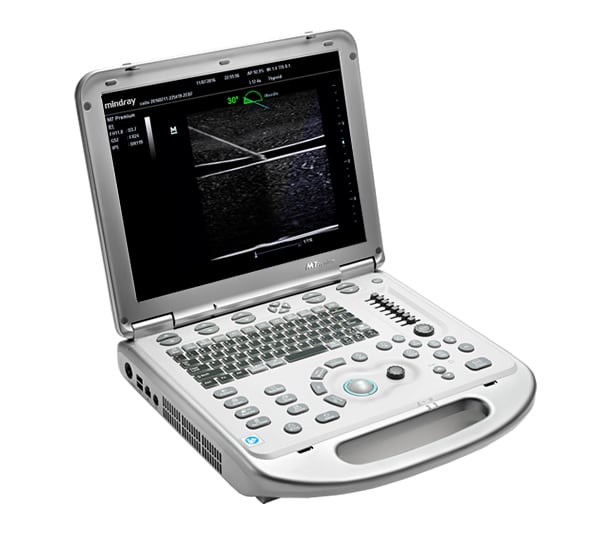

With its ergonomic mobile trolley same with performance and features comparable to that of conventional cart-based systems, the M7 Premium provides you mobility with power and improves your productivity. To sum it up, the M7 delivers you the power and productivity of a full-sized system in a hand-carried size.

Ergonomics

- Lightweight Portable design

- Special designed cart with built-in handle

- Uninterrupted scanning with rechargeable battery

- 15″ LCD